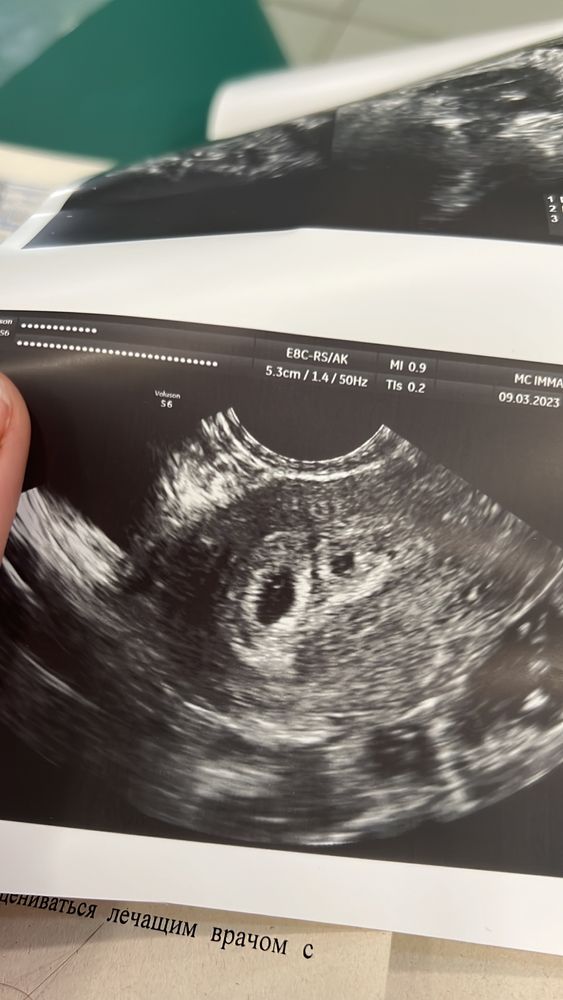

Да, это плодное яйцо. Простите потихоньку, потом повязаться внутри колечко(желточный мешок), недель в 7 уже точно видно эмбрион и сердцебиение. Пусть малютка развивается, не бегайте очень часто на узи.

ИзображениеВот так выглядит мешочек, в черном пятне, если приглядеться маленькое тоненькое колечко

Ксюня, еще слишком маленькое плодное яичко, чтоб там было видно, не переживайте. Примерно при размере 12мм уже видно

У меня в 5,4 пя увидели (как у вас вот) а в 7,1 уже эмбриончик с сердцебиением

Судя по буквам GS это гестационный пузырь (мешок) это полость жидкости, которая окружает эмбрион. Пока эмбриончика у вас по узи не видно (срок скорее всего маленький)